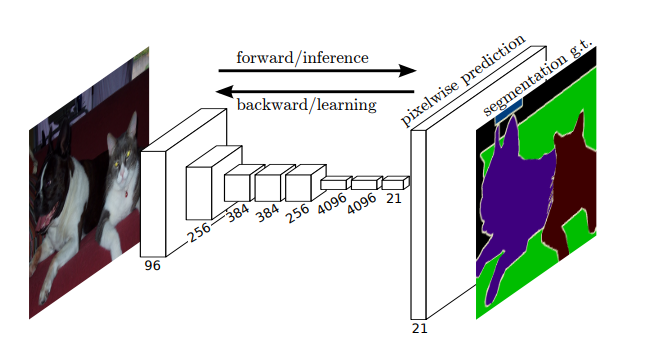

fcn

FCN(Fully Convolutional Network,完全卷积网络)是一种专门用于图像分割任务的神经网络架构,它的设计思想是在传统的卷积神经网络(CNN)的基础上,去除全连接层,并用卷积层替代,使得网络能够接受任意尺寸的输入并生成相同尺寸的输出。

FCN的核心结构由多个卷积层组成,卷积层对输入图像进行特征提取,逐层提取更加抽象的特征信息。通过这种方式,FCN能够生成高分辨率的特征图,并在此基础上进行像素级的分类,进而实现图像分割。

首先,FCN使用了一系列标准的卷积层来进行初步的特征提取,接着这些卷积层会产生较低分辨率的特征图。为了保持输出的空间分辨率,FCN采用了一种上采样(或反卷积)操作。反卷积层通过学习一个转换映射,将低分辨率的特征图恢复到较高的分辨率,从而得到像素级的分类输出。这种上采样操作可以逐步恢复图像的空间结构,使得最终输出的分割结果具有和输入图像相同的尺寸。

在FCN中,卷积层的输入和输出都是特征图,不同于传统CNN中的输入为图像、输出为分类结果。通过这种结构,FCN不仅能够进行像素级分类,而且能够适应不同尺寸的图像输入,从而提高了网络的灵活性和应用范围。

此外,FCN还采用了一些策略来优化网络性能。为了进一步提高分割精度,FCN使用了跳跃连接(skip connections),通过将低层次的特征图与高层次的特征图结合,网络能够更好地捕捉细节信息。这些跳跃连接帮助网络弥补了上采样过程中可能丢失的空间细节,使得分割结果更加精细。

总的来说,FCN是一种非常有效的图像分割模型,能够实现端到端的训练,并能够处理各种不同大小的图像输入。通过卷积层、上采样层和跳跃连接的结合,FCN能够生成高质量的图像分割结果,并且在许多实际应用中取得了优异的表现。